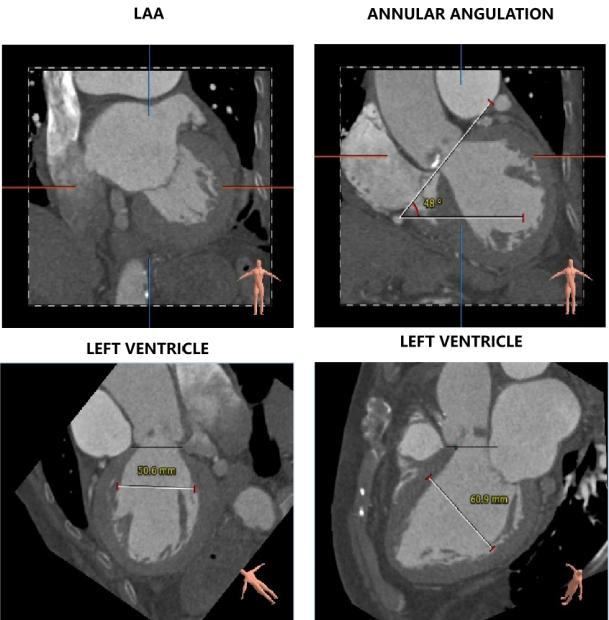

主动脉根部评估

CT数据显示该患者为三叶三窦式主动脉瓣。

左冠开口高度11.0mm,右冠开口高度17.9mm,左冠高度较低,根据瓦氏窦内径和瓣叶长度综合判断,左冠存在一定堵塞风险;左室腔增大,心室壁未见明显增厚。

1、患者主动脉根部钙化分散少量,瓣叶增厚明显,锚定力存在不足;

2、患者左冠开口较低,结合瓦氏窦内结构,存在一定左冠封堵危险;

• 在术前评估阶段,首先通过心电图及超声探查,对患者心力储备、心脏电生理状况有了一个基本的把握,明确了患者自身的心力储备情况。之后的CTA评估,通过瓣环上平面测量,提示了瓣叶钙化轻微,主动脉根部锚定力较弱。于术前明确了瓣中瓣发生可能性,为术中的快速决策提供了可能。